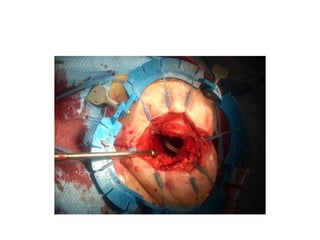

PERINEAL PHASE

• Anus closed with purse string suture.

• Tear drop incision made encircling anus unto tip of cocyx.

• External sphincter identified and dissection continued outside

levator muscle .

• Levator muscles are followed until their origin in pelvic

sidewall (white line)

• Mesorectum entered just anterior to coccyx or through

sacrococcyxeal junction after removing coccyx.

• Pelvic floor is divided (levator)

• Dissection continues anteriorly onto the prostate /vagina

• Cylindrical specimen is excised.